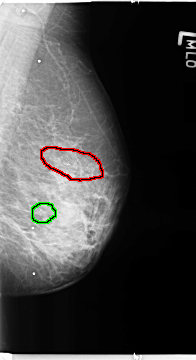

Volume: benign_04 Case: B-3364-1

B_3364_1.LEFT_MLO

FILE: B_3364_1.LEFT_MLO.OVERLAY

TOTAL_ABNORMALITIES 2

ABNORMALITY 1

LESION_TYPE CALCIFICATION TYPE PLEOMORPHIC DISTRIBUTION CLUSTERED-SEGMENTAL

ASSESSMENT 4

SUBTLETY 4

PATHOLOGY BENIGN

TOTAL_OUTLINES 1

BOUNDARY

ABNORMALITY 2